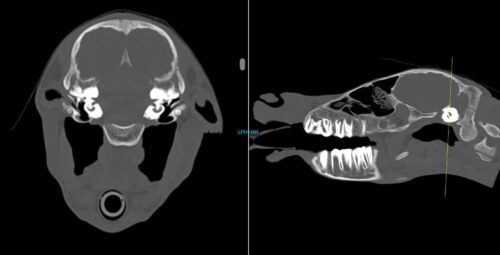

These images show a CT of the neck of a horse. The image on the left is a bird’s eye view of the vertebrae of the neck and the image on the right shows an image taken from the side of the horse’s neck.